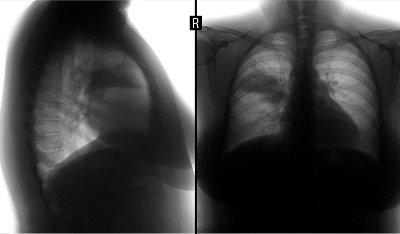

While many of the symptoms of bronchiectasis are similar to those of other conditions, some are unique to this condition. A common symptom is coughing up mucus, called sputum. The amount and color of sputum produced by individuals with bronchiectasis vary significantly. Patients with this condition tend to produce more mucus than those without it. Oren Zarif